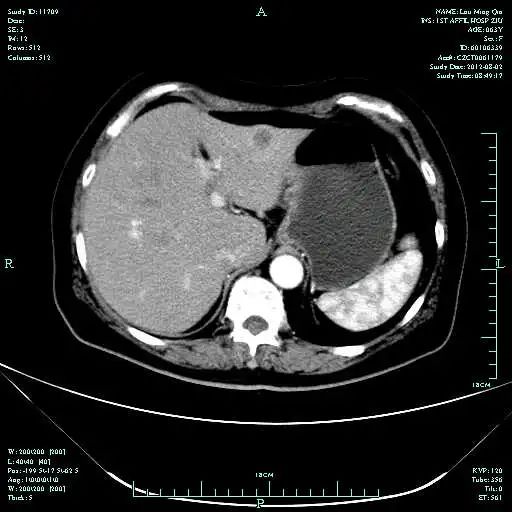

CT-T

CT-H1

MR-H1

影像学检查结果评估:cPD。

TOGA研究是第一个使用HER2抑制剂曲妥珠单抗治疗不能手术的局部晚期、复发或转移的HER2阳性胃癌患者的Ⅲ期临床研究。TOGA研究结果显示,IHC2+/FISH阳性或者IHC3+的患者与对照组相比,OS分别为16.0个月和11.8个月(HR为0.65)。曲妥珠单抗联合化疗显著提高了HER2阳性晚期转移性胃癌的治疗缓解率和总体生存率。2012年8月,曲妥珠单抗治疗HER2阳性转移性胃癌适应症在我国获批。对该患者进行病理切片会诊,幸运的是其HER2检测为阳性。随即进行靶向联合化疗治疗,三个周期后,肝转移灶消失,曲妥珠单抗治疗效果显著。九个周期的靶向治疗联合放化疗后,疗效评估cPR,随即行手术治疗。